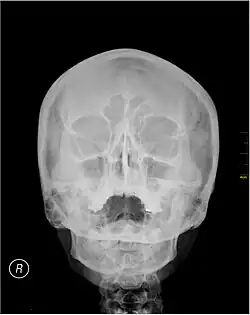

Waters' view

Waters' view (also known as the occipitomental view or parietoacanthial projection) is a radiographic view of the skull. It is commonly used to get a better view of the maxillary sinuses. An x-ray beam is angled at 45° to the orbitomeatal line. The rays pass from behind the head and are perpendicular to the radiographic plate. Another variation of the waters places the orbitomeatal line at a 37° angle to the image receptor. It is named after the American radiologist Charles Alexander Waters.

Structures observed

Waters' view can be used to best visualise a number of structures in the skull.

- Maxillary sinuses.

- Frontal sinuses, seen with an oblique view.

- Ethmoidal cells.

- Sphenoid sinus, seen through the open mouth.

- Odontoid process, where if it is just below the mentum, it confirms adequate extension of the head.

The Waters' view may not show the frontal sinus in detail.[1]

Procedure

Typically, the x-ray beam is angled at 45° to the orbitomeatal line.[3] Another variation of the waters places the orbitomeatal line at a 37° angle to the image receptor,[4] or 30°.[5]